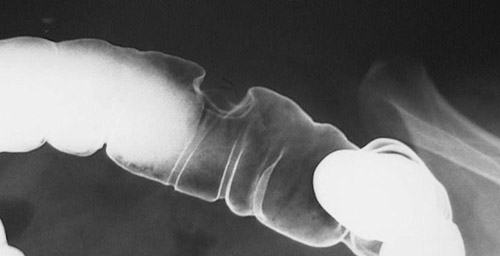

A sessile mass in the descending colon is seen in this barium enema. The mass is larger than 2 cm, most consistent with an adenocarcinoma.